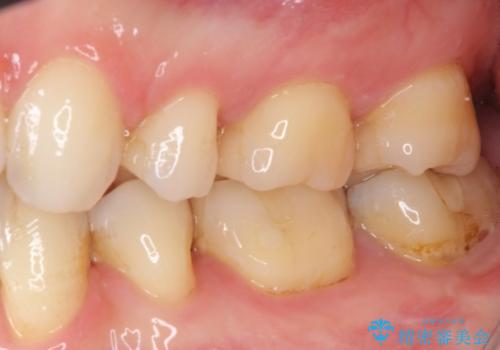

- 下の奥歯に虫歯ができてしまったとのことで来院された患者様です。

他にも気になる歯はありましたが、急を要する1歯のみをセラミックインレーにて修復治療を行うこととしました。

奥歯において、隣の歯と接触する部分に虫歯が及んでしまった場合、その場で充填を行う処置(コンポジットレジン修復)ですと、充填の縁に大きなギャップが生じてしまう可能性が高く、2次的な虫歯を引き起こすことになります。

また、処置した歯の後方にある歯は保険診療で使用するレジンインレーが装着されていますが、縁に虫歯が出来はじめていることが分かります。

再治療が必要とならないようにするにはどうしたらよいか、担当医とよく相談されると良いと思います。